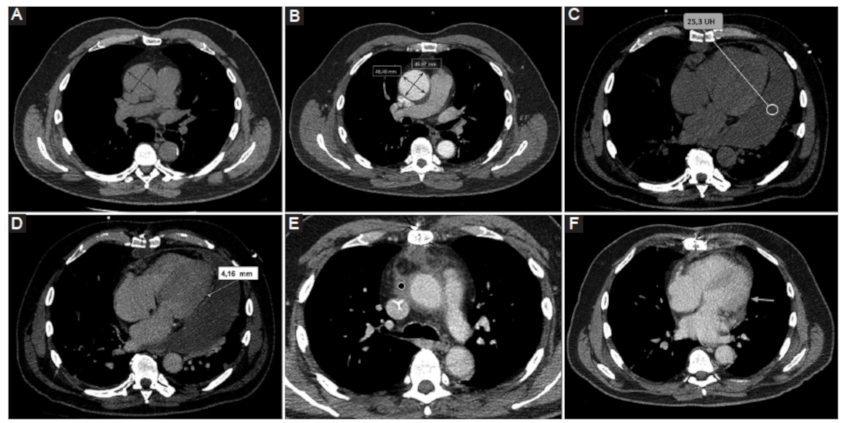

Hemopericardio

Se define como la presencia de contenido hemático en el espacio pericárdico, que puede darse en diversos contextos clínicos:

Iatrogénico: en este grupo se engloban el hemopericardio secundario a procedimientos cardiacos invasivos tales como la intervención coronaria percutánea o la colocación de marcapasos (Fig. 9); o como consecuencia de una cirugía cardiovascular (Fig. 10).

Trauma torácico: fuerzas de alta energía que llevan a la presencia de hemopericardio, ruptura pericárdica, taponamiento cardiaco y/o herniación.

Síndrome aórtico agudo: en este contexto, el hemopericardio ocurre con una frecuencia estimada de entre un 17-45%, hecho que contraindica la pericardiocentesis y representa una emergencia clínica (Fig. 11) (6.

Los métodos por imágenes están indicados para la valoración de cuantía y severidad con un nivel de evidencia B clase 1 según las guías vigentes6. Según la serie de Rifkin et al. (3, la TCMC, entre otras cosas, permite identificar la presencia de hemopericardio ante una densidad promedio mayor a 30 UH con una sensibilidad cercana al 100%.

Pericarditis constrictiva

Representa una condición clínica resultante de una menor distensibilidad del pericardio2,14. Si bien su etiología es multifactorial, se asocia con mayor frecuencia al antecedente de pericarditis autoinmune, neoplasias del pericárdico y pericarditis bacteriana6,15.

Los síntomas clásicos de presentación son secundarios a falla diastólica, con signos de insuficiencia cardiaca derecha en ausencia de patología cardiaca subyacente6.

La TCMC presenta gran rédito para la identificación de la pericarditis constrictiva, así como también para discriminar los hallazgos de su principal diagnóstico diferencial que es la miocardiopatía constrictiva (Fig. 12). Cabe remarcar que si bien ambas entidades presentan similar escenario clínico, la pericarditis constrictiva es potencialmente tratable, a diferencia de la miocardiopatía constrictiva, que se asocia con un pronóstico desfavorable6.

Entre los hallazgos clásicos visualizados por TCMC se mencionan:

Engrosamiento pericárdico mayor a 4 mm. Este hallazgo resulta poco sensible, ya que puede presentarse con pericardio de grosor conservado16.

Calcificación de las hojas pericárdicas16.

Signos indirectos como reducción de volumen del ventrículo derecho de morfología tubular16.

Cabe mencionar que el engrosamiento y la presencia de calcificaciones resultan datos muy sugestivos de esta entidad, pero con limitada sensibilidad. En este sentido, Talreja et al. (16, en su serie de 143 pacientes con diagnóstico definitivo de pericarditis constrictiva, encontraron que un 18% de los casos se presentó con grosor pericárdico normal, y entre un 30-40% de los casos se presentó con calcificaciones pericárdicas.

La TCMC permite además una correcta evaluación prequirúrgica, considerando la pericardiectomía como tratamiento de elección2.